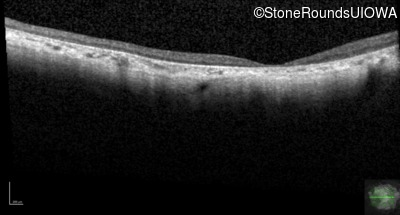

Optical Coherence Tomography - Left - 10/200 -3 sc

Exemplar / OCT Stack